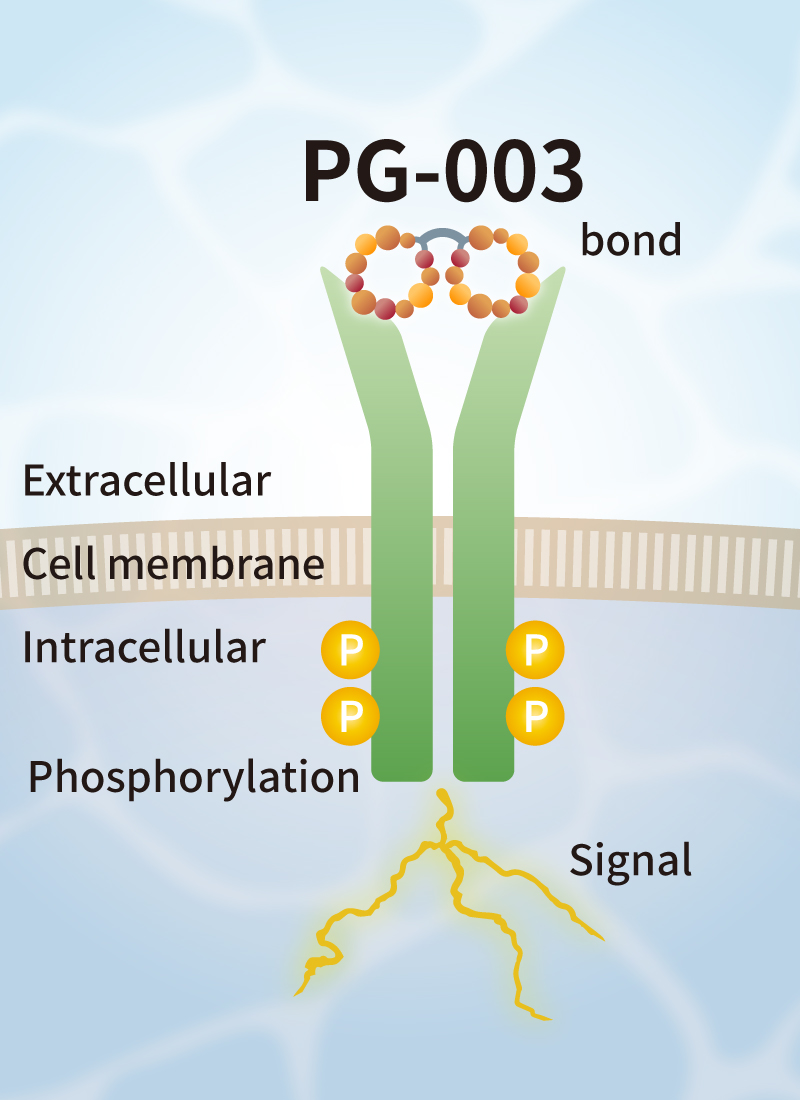

Solve challenges of conventional growth factors

Challenges of conventional growth factors

Currently, FBS and recombinant growth factors are used for cell culture. However, such products have some challenges such as variation in quality among production lots, contamination by biological impurities, low stability, and extremely high prices.